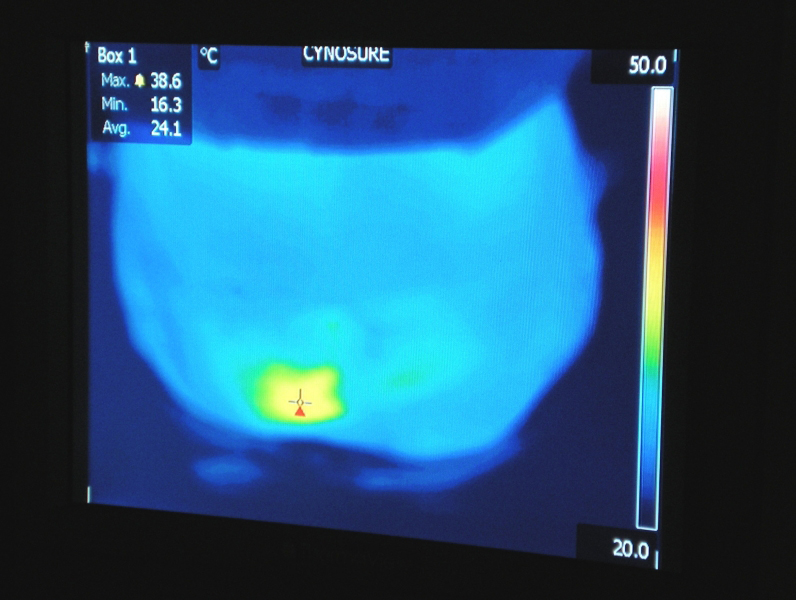

- Thermal camera is used for sensing the true temperature of the skin & tissue. Dr. Petti is very advanced and on the cutting edge of technology. She has incorporated lasers in her practice since 1994.